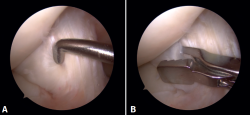

No se evidenciaron alteraciones significativas en el estudio radiológico simple realizado. En la RM se evidenció la presencia de un ganglión del LCA con afectación de su fascículo posterolateral (Figura 1).

Figura 1. Imagen de resonancia magnética del quiste sinovial localizado en el ligamento cruzado anterior. A: secuencia PDW SPIR en corte sagital de la rodilla; B: secuencia PDW SPIR en corte coronal de la rodilla.